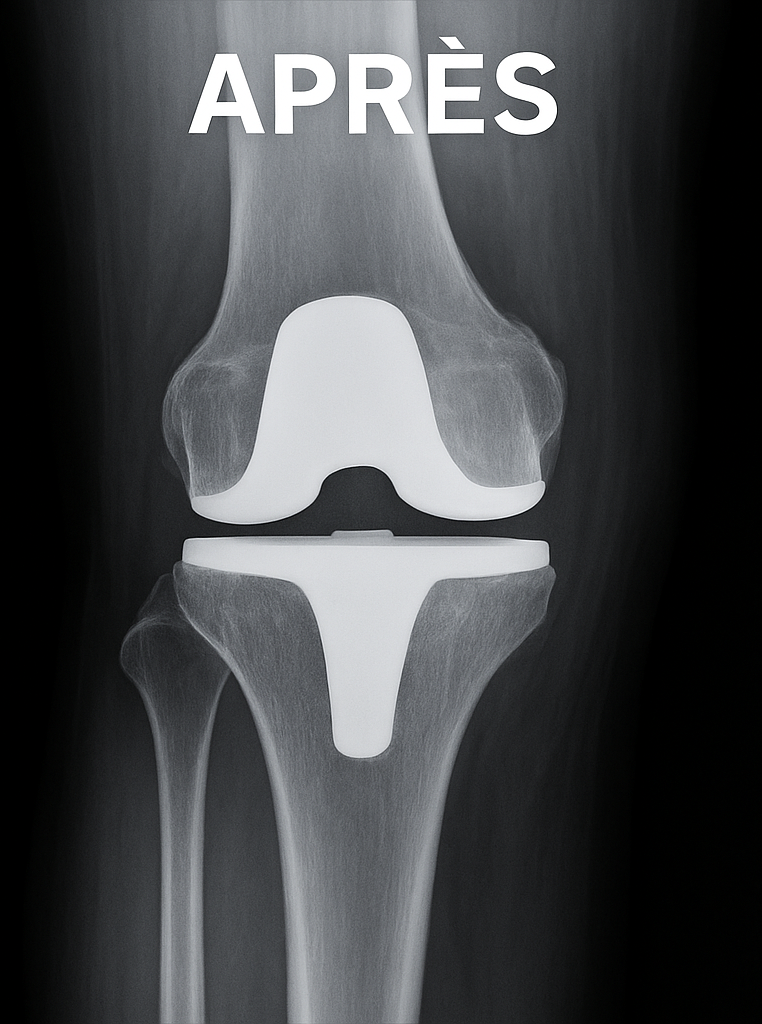

Prothèse du genou